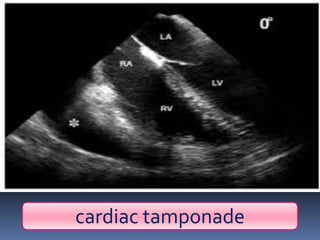

Abnormal Findings Un equalityof chest movement Dullness on percussion Normal air entry ,muffled heart sounds Tachypenic, congested neck veins Cardiac tamponade pericardiocentesis

▪ (almost alwaysseen with a penetrating wound) ▪ Beck’s triad: Hypotension distended neck veins Muffled heart sounds Pulsus paradoxus

Cardiac tamponade

pericardiocentesis

▪ (almost always seen with a penetrating

wound)

▪ Beck’s triad:

Hypotension

distended neck veins

Muffled heart sounds

Pulsus paradoxus